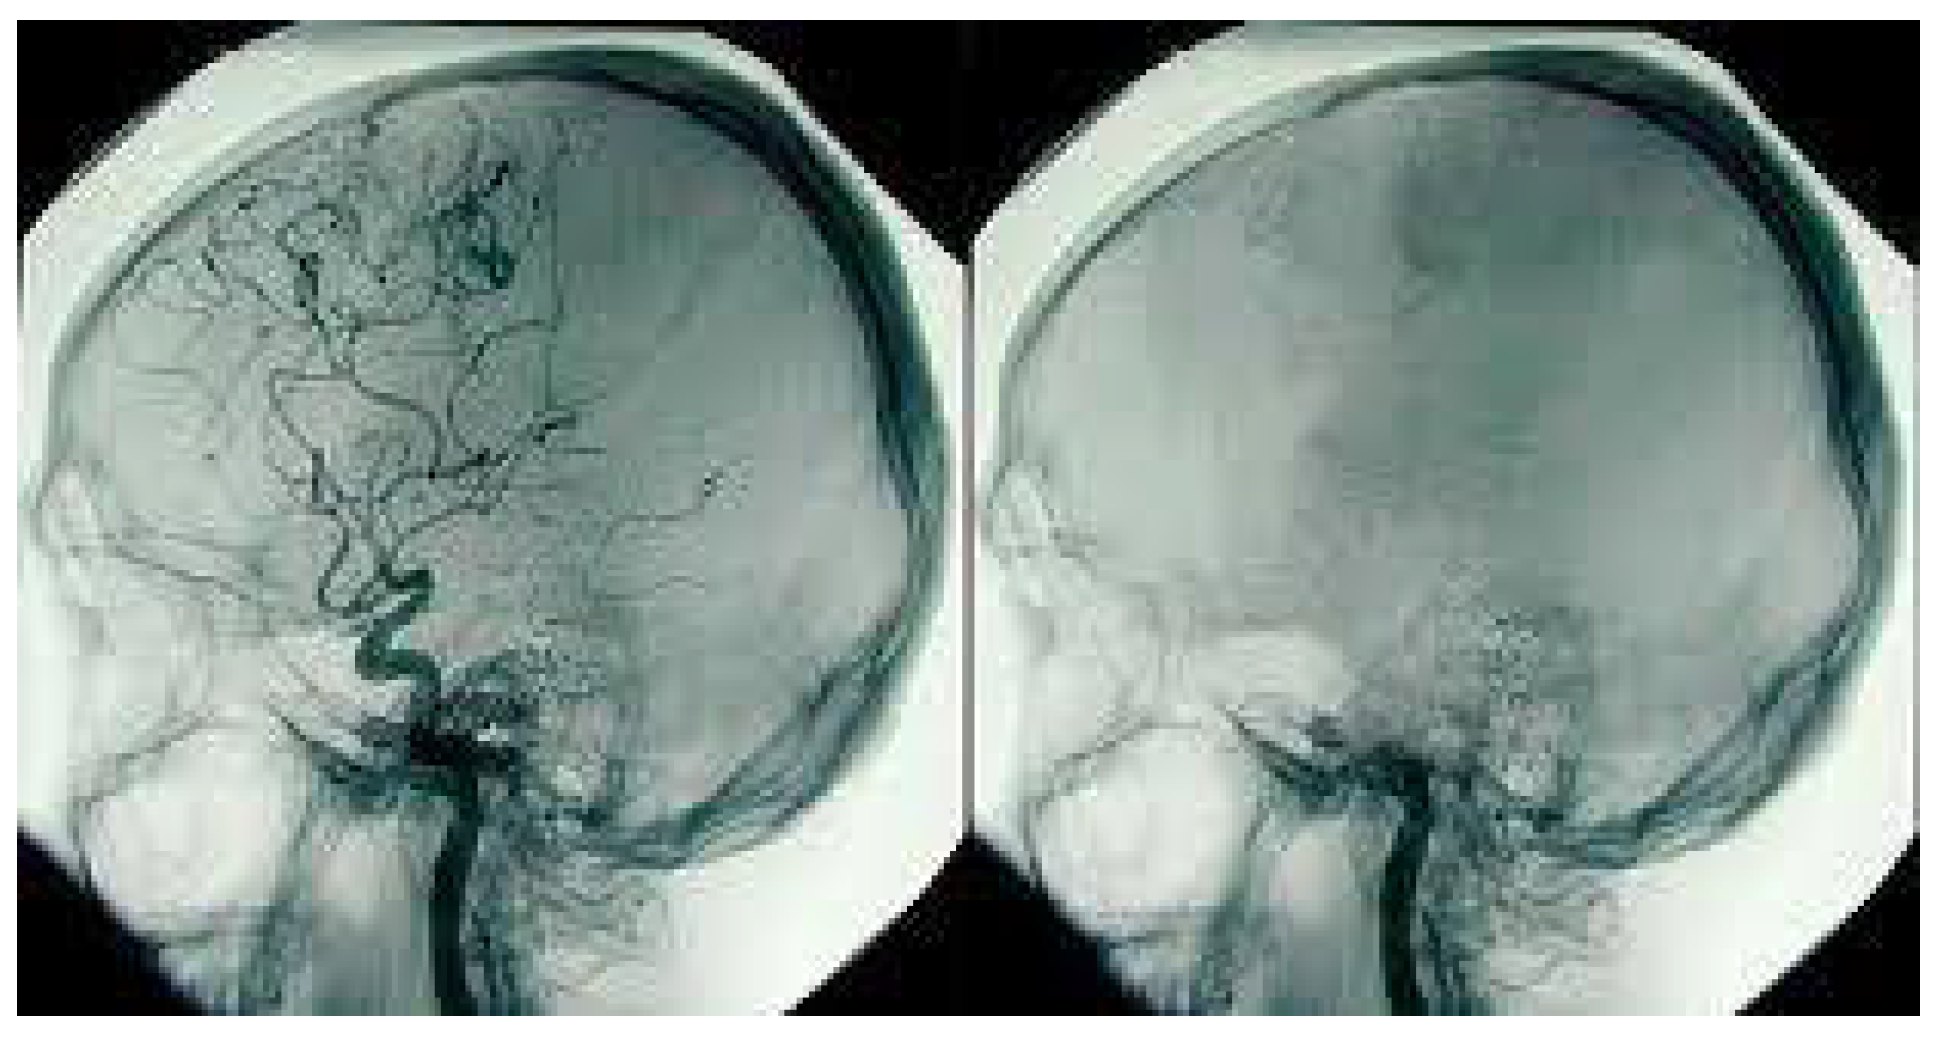

• This further exerts pressure on the brain, causing further brain injury. The doctors, at this stage, are working on the patient with various treatment methods. If these treatments fail, the brain may get so damaged that at some stage, all functions of the brain will be lost. Once a brain cell dies it is permanently lost; the body cannot regenerate brain cells. The high pressure inside the skull will stop all blood flow into the skull; this can be diagnosed by an angiogram (Figure 2) or a special brain scan (Figure 3).

Often clinicians can declare death after clinical testing. Sometimes, when clinical testing cannot be performed or clinicians are not satisfied during the process of testing (e.g., if the patient could not complete an Apnoea test), clinicians may request a radiological investigation to confirm the ‘absence of blood flow to the brain’, as mentioned previously—this process involves transporting the patient to the radiology department and undertaking an angiogram or a Technesium brain scan (neuroimaging). These investigations are then reported by appropriately trained radiologists, upon which the clinicians then decide whether to determine brain death.

Figure 3. TC99 scan of the brain of a brain-dead person showing nil evidence of brain activities. Photo Source: Australian Donor Awareness Programme and Training (ADAPT).